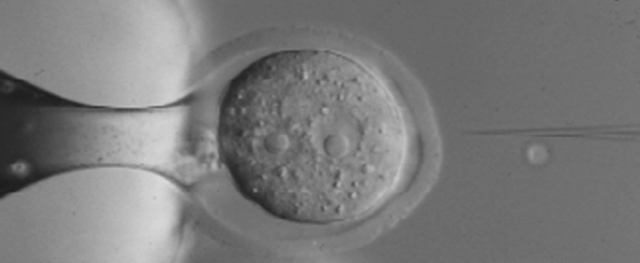

Past research - microinjection